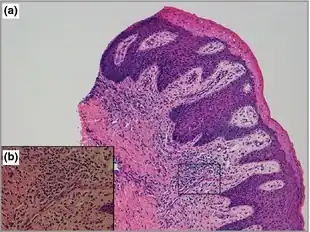

CHILD syndrome without hemidysplasia-a, b) Skin biopsy show features compatible with ichthyosiform dermatosis: acanthosis and extension of rete pegs of epidermis, marked parakeratotic scaling with loss of granular layer

The symptoms would appear at birth or shortly after birth. The combination of physical symptoms on the child would suggest they have CHILD syndrome. A skin sample examined under a microscope would suggest the characteristics of the syndrome and an X-ray of the trunk, arms, and legs would help to detect underdeveloped bones. A CT scan would help detect problems of the internal organs.